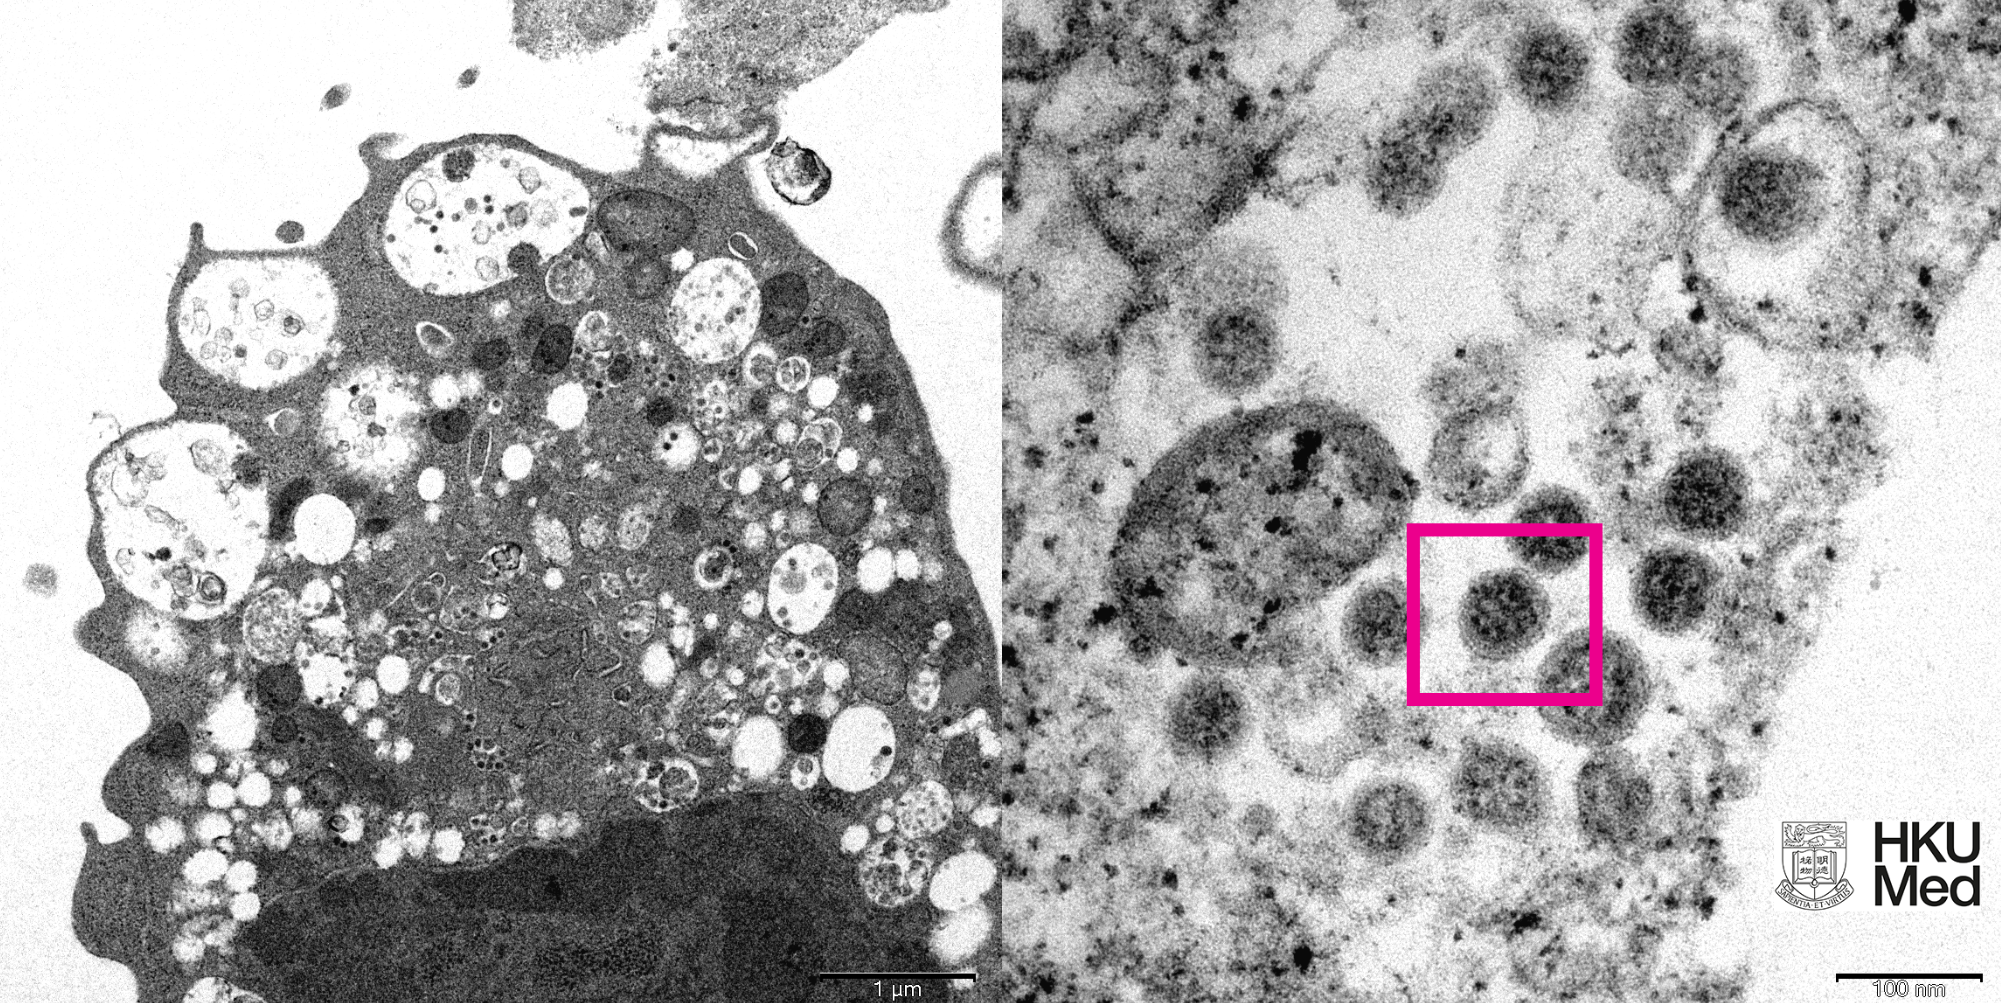

Ερευνητές της ιατρικής σχολής στο πανεπιστημίου του Χογκ-Κογκ απομόνωσαν και φωτογράφισαν την παραλλαγή Όμικρον του κορωνοϊού χρησιμοποιώντας ηλεκτρονικό μικροσκόπιο σάρωσης.

(Δεξιά) Μεγεθυμένη λεπτομέρεια του κυττάρου όπου φαίνονται τα συσσωματώματα ιικών σωματιδίων με τις πρωτεινικές ακίδες σχήματος κορώνας στην επιφάνειά τους (κόκκινο πλαίσιο) – κάντε κλικ πάνω στην εικόνα για μεγέθυνση. Photo credit: Professor John Nicholls, Clinical Professor of Department of Pathology; and Professor Malik Peiris, Tam Wah-Ching Professor in Medical Science and Chair Professor of Virology, School of Public Health, HKUMed; and Electron Microscope Unit, HKU.